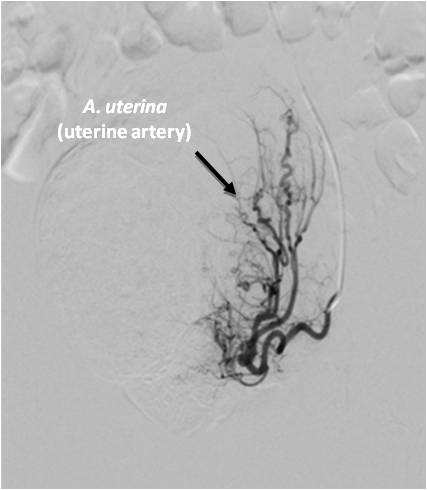

Fig. 1. A selective angiogram of the left uterine artery of a female patient G., 51 years old.

During the UAE in patients of the older age group, alterations of vessels in the form of pronounced tortuosity of the iliac and uterine arteries were recorded in 100% of cases (Figure 1). More often, these anatomical vascular alterations are associated with pregnancies, when the pelvic arteries lengthen, and then significantly decrease in size after childbirth. Difficulties in superselective catheterization of the uterine artery were also encountered in patients over 50 suffering from arterial hypertension. The resulting tortuosity of the iliac arteries, especially in combination with a high position of the aortic bifurcation and the sharp angle of its division, significantly hampered manipulation on the contralateral side. These features of vascular anatomy were a cause of failure of selective catheterization of the uterine arteries on one of the sides in 17 (1.6%) patients with use of transfemoral access.